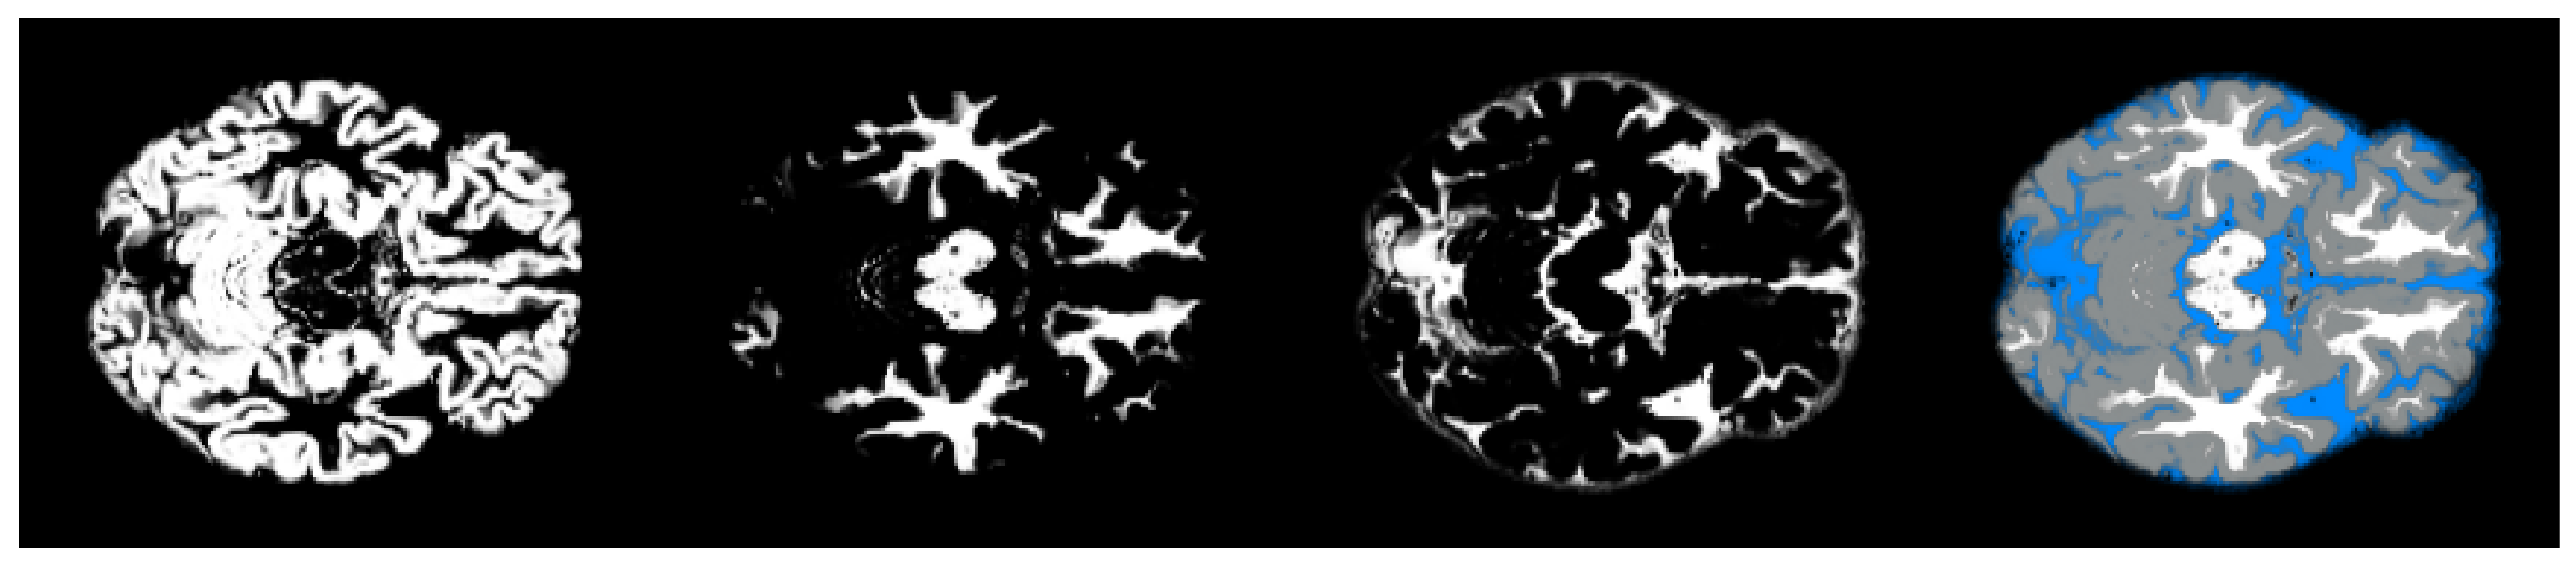

- We have introduced the notion of significant pixels, i.e., the pixels of the MRI images where the white (resp. gray) matter decays in the considered two-year time span, significantly differ between and subjects. The number of significant pixels, in the brain slices where the phenomenon mostly appeared, according to the different values obtained after performing a permutation test on all the pixels of the images, i.e., , , and , was about 4%, 2%, and 1.5% of the totality of the white matter and slightly more, i.e., 6%, 4%, and 2.5%, of the totality of the gray matter. Such a small number of significant pixels is sufficient to discriminate between and , as reported in Table 2 and Table 3, using the K-means clustering technique. Not surprisingly, when considering the white matter, all the and subjects were correctly clustered, i.e., the white matter decay of subjects significantly differed from that of ones. On the other hand, when considering gray matter, the subjects were correctly classified, while 6 of the 40 subjects were assigned to the class, with a percentage of error of 15%. This can be ascribed to the fact that Alzheimer’s disease strongly impacts on the white matter first, and later leads to the decay of the gray matter.We also underline that, according to the wide and consolidated literature, the most involved areas of the brain affected by Alzheimer’s decay are the medial portion of the temporal lobe, where the hippocampus, amygdala, entoryl cortex, and parahippocampal cortex reside. These areas are located inside the selected slice intervals where most of the significant pixels were detected. As an example, Figure 7 shows the significant pixels of slice 58, where a peak in the white and gray matter occurred, with the involved brain areas highlighted.